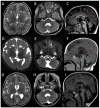

The TUBA1A gene encodes tubulin alpha-1A, a protein that is highly expressed in the fetal brain. Alpha- and beta-tubulin subunits form dimers, which then co-assemble into microtubule polymers: dynamic, scaffold-like structures that perform key functions during neurogenesis, neuronal migration, and cortical organisation. Mutations in TUBA1A have been reported to cause a range of brain malformations. We describe four unrelated patients with the same de novo missense mutation in TUBA1A, c.5G>A, p.(Arg2His), as found by next generation sequencing. Detailed comparison revealed similar brain phenotypes with mild variability. Shared features included developmental delay, microcephaly, hypoplasia of the cerebellar vermis, dysplasia or thinning of the corpus callosum, small pons, and dysmorphic basal ganglia. Two of the patients had bilateral perisylvian polymicrogyria. We examined the effects of the p.(Arg2His) mutation by computer-based protein structure modelling and heterologous expression in HEK-293 cells. The results suggest the mutation subtly impairs microtubule function, potentially by affecting inter-dimer interaction. Based on its sequence context, c.5G>A is likely to be a common recurrent mutation. We propose that the subtle functional effects of p.(Arg2His) may allow for other factors (such as genetic background or environmental conditions) to influence phenotypic outcome, thus explaining the mild variability in clinical manifestations.